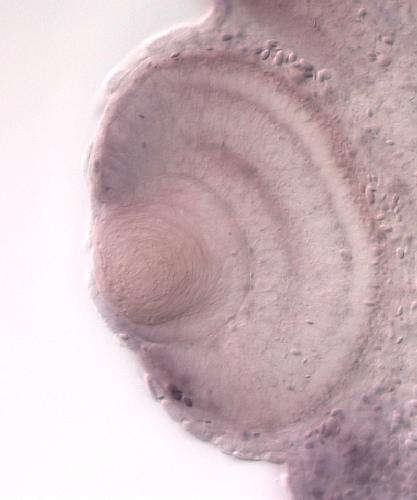

tapbp

TAP binding protein (tapasin)

tapbp encodes a membrane‑associated endoplasmic reticulum chaperone that forms part of the peptide‑loading complex for major histocompatibility complex class I molecules, facilitating peptide binding a...[+]